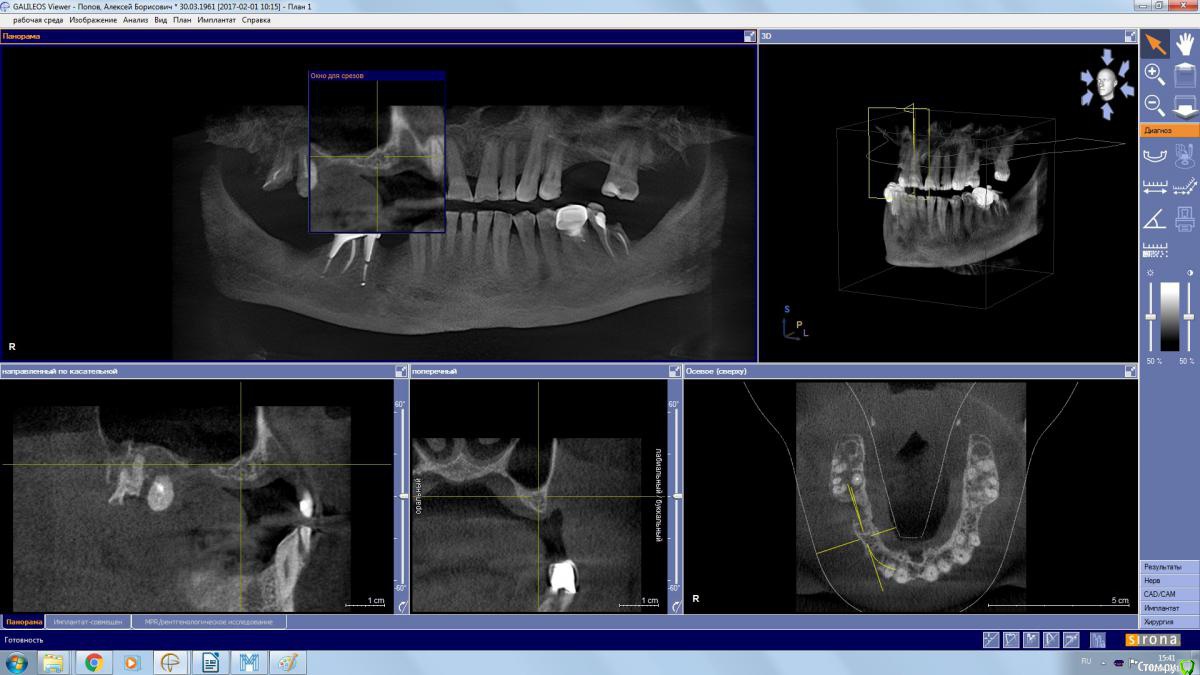

kamranchick Опубликовано 2 апреля, 2017 Поделиться Опубликовано 2 апреля, 2017 (изменено) Пациент обратился с целью восстановления жевания.удалял 16 зуб в поликлиннике, ему долбили, потом в ЧЛХ доставали что то).На кт вот такая ситуация, как посоветуете поступить? PS 1.7 и 1.8 зуб удалил. Изменено 2 апреля, 2017 пользователем kamranchick Ссылка на комментарий

stommm Опубликовано 2 апреля, 2017 Поделиться Опубликовано 2 апреля, 2017 Где окно расщеплять лоскут остро что бы часть осталась на поверхностном лоскуте, часть ввернуть в синус. Наверное можно совместить с НКР фронтальнее. З.Ы. сложно по сироне что-то планировать, самый неудобный вьюер имхо 1 Ссылка на комментарий

колесников Опубликовано 2 апреля, 2017 Поделиться Опубликовано 2 апреля, 2017 А в чем вопрос? Пазуха чистая,можно пробовать . Ссылка на комментарий

kamranchick Опубликовано 2 апреля, 2017 Автор Поделиться Опубликовано 2 апреля, 2017 Да дыры какие то и на окклюзионной поверхности и сбоку) это и отпугнуло Ссылка на комментарий